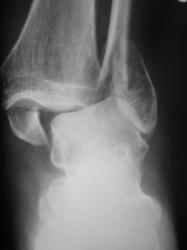

Перелом обеих лодыжек со смещением, наружно-пронационный вывих стопы.

А передний край пилона разве не сломан? Или это медиальная лодыжка наслаивается?